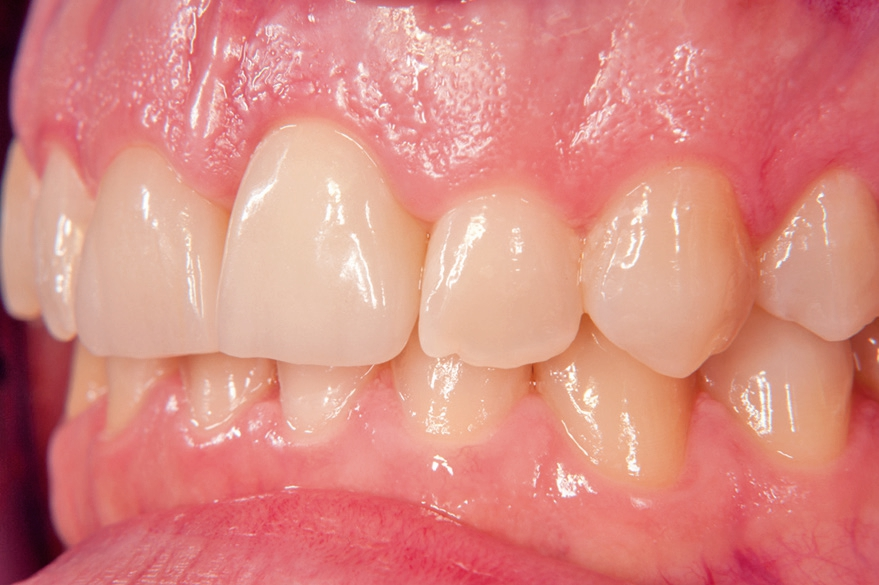

Gleichzeitig mit der prothetischen Versorgung des Implantats wurde auch für Zahn 11 ein Veneer geplant. Zum Einsatz kam ein Zeramex T Implantat Durchmesser 5,5 mm, Länge 12 mm. Für die Kronenversorgung wurde ein mit e. Max überpresstes CAD-Abutment gewählt. Während der Einheilphase des Implantats kam eine Sunflex-Prothese zum Einsatz.